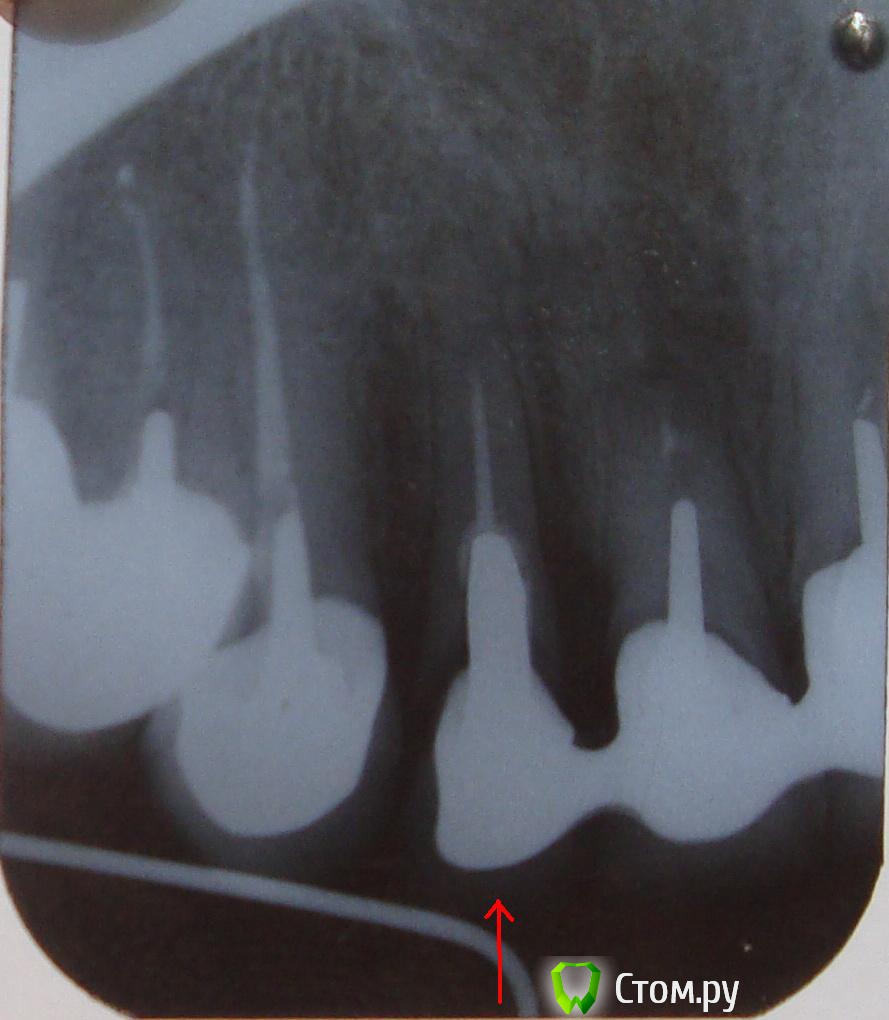

nu_zaec Опубликовано 15 июля, 2014 Автор Поделиться Опубликовано 15 июля, 2014 Здравствуйте, состав Вам нужно узнать у Своего Врача. Если хотите комментариев. , выкладывайте фото и снимки. http://forum.stom.ru/topic/20613-sovety-patcientam-obiazatelno-k-prochteniiu/Здравствуйте. Я ничего не могу узнать у того врача. Дело было 18 лет назад. Снимок прилагаю. Речь о верхней двойке справа. А какие варианты сплавов вообще были в то время? Их было много, тех вариантов? Ссылка на комментарий